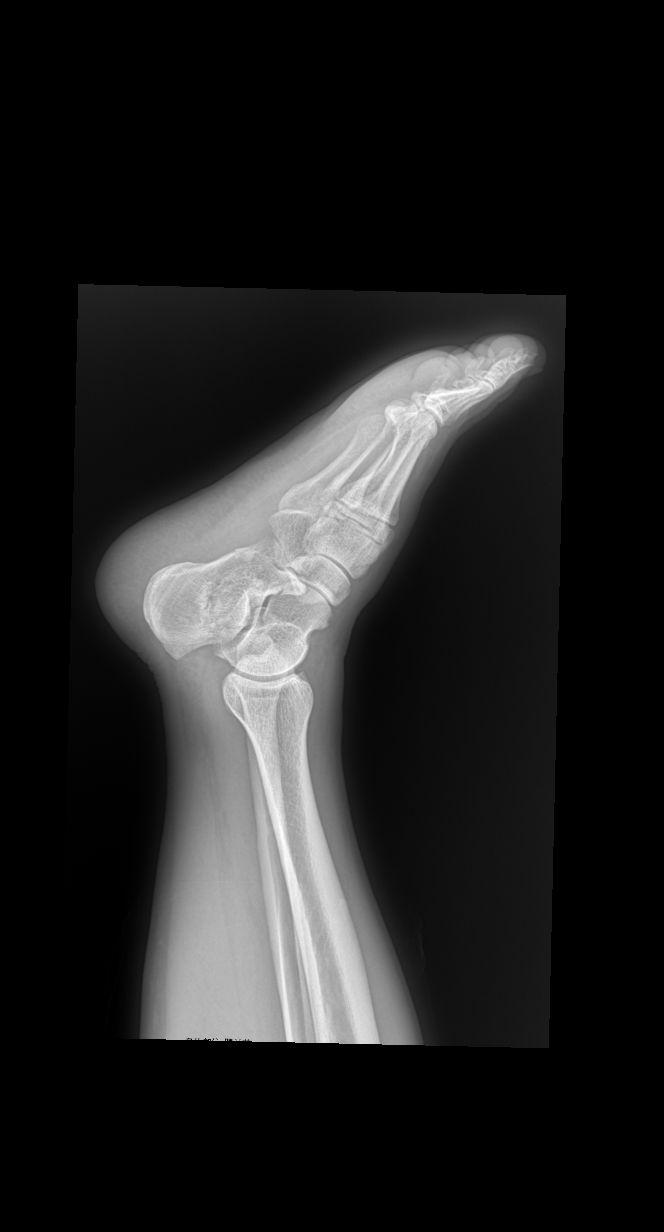

从梯子上落下 外伤就诊